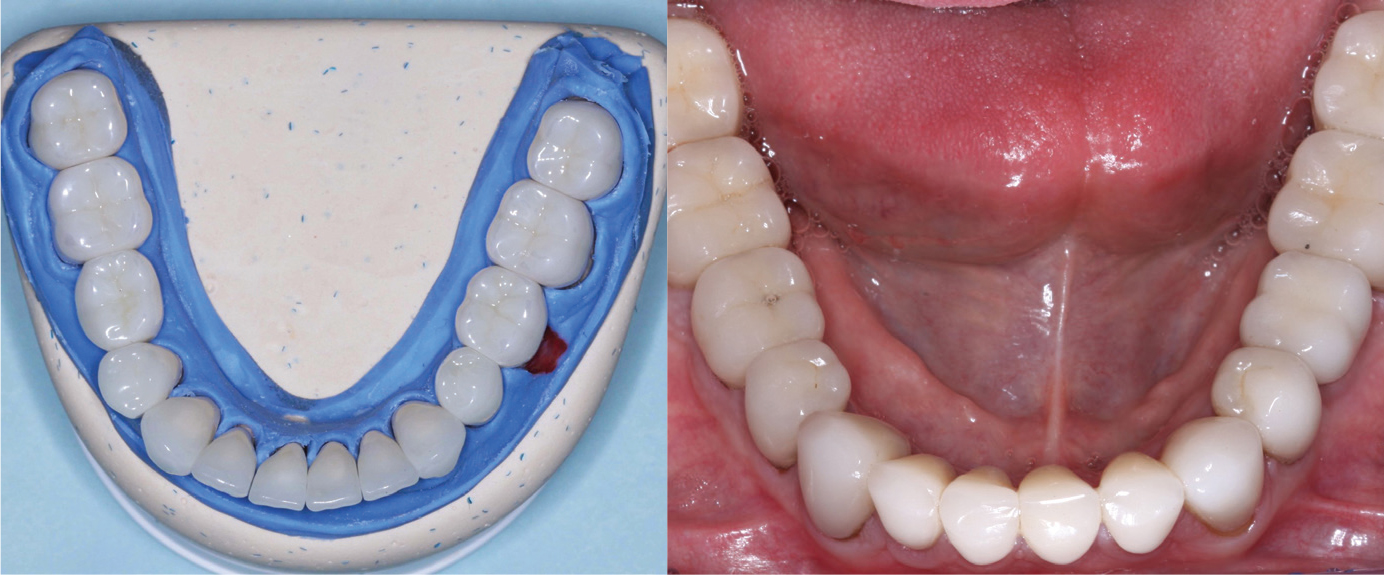

Figures 1 and 2: The restorations on the molars are Class 5 zirconia colored in the presintered stage, nonglazed or superficially stained. They are polished only. The restorations cannot be differentiated from the lithium disilicate restorations on the remainder of the teeth and implants. Note the lack of simulated caries on the occlusal surfaces, which is discouraged. Natural teeth without caries do not have occlusal color. Technicians: Jed and John Archibald; Archibald Associates; Orem, Utah. Clinician: Gordon Christensen, DDS, prosthodontist.